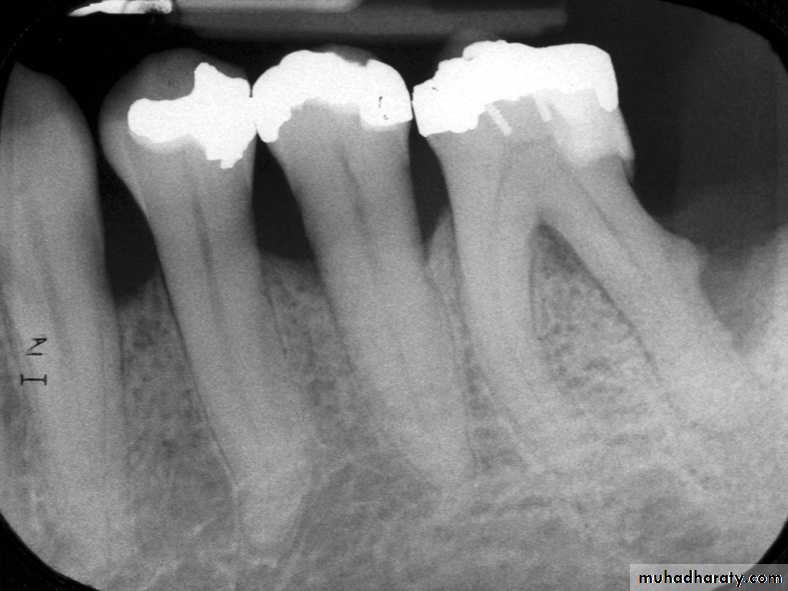

3. Radiographic changes: Radiograph may shows a large cavity or restoration

• Radiographic changes: small change to large periapical radiolucency

• Radiography helpful in determining the affected tooth as it shows a cavity or evidence of bone destruction at root apex.

• Mostly discovered on routine radiographic examination

• The earliest change in the periodontal ligament is found to be thickening of ligament at the root apex

• Lesion may be well circumscribed or poorly defined

• Size may vary from small lesion to large radiolucency exceeding more than 2 cm in diameter.